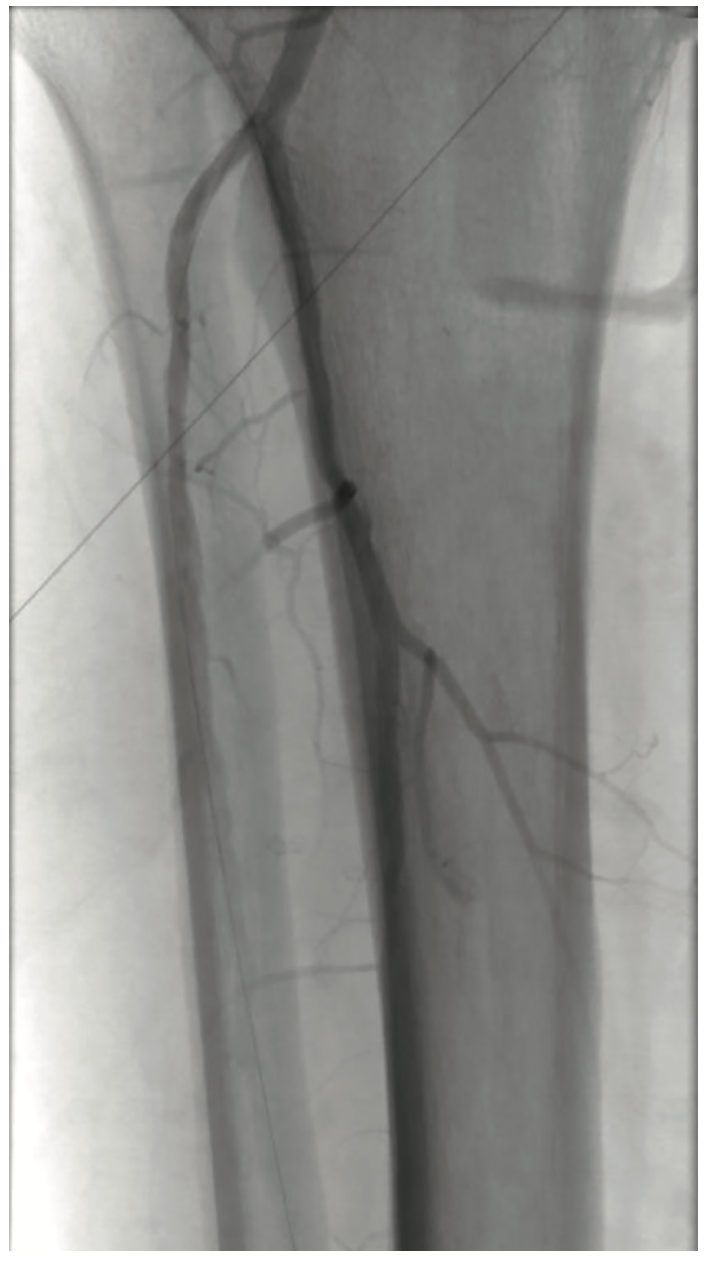

Following optimization of the inflow disease, a 3 mm x 120 mm Serranator balloon was used with overlapping, sequential inflations up to 8 atm in the AT artery. The same balloon was then utilized in the TPT at a maximum of 6 atm (Figure 7). Both AT and TPT lesions had 0% stenosis and no dissections, perforations, or recoil were observed (Figure 8).